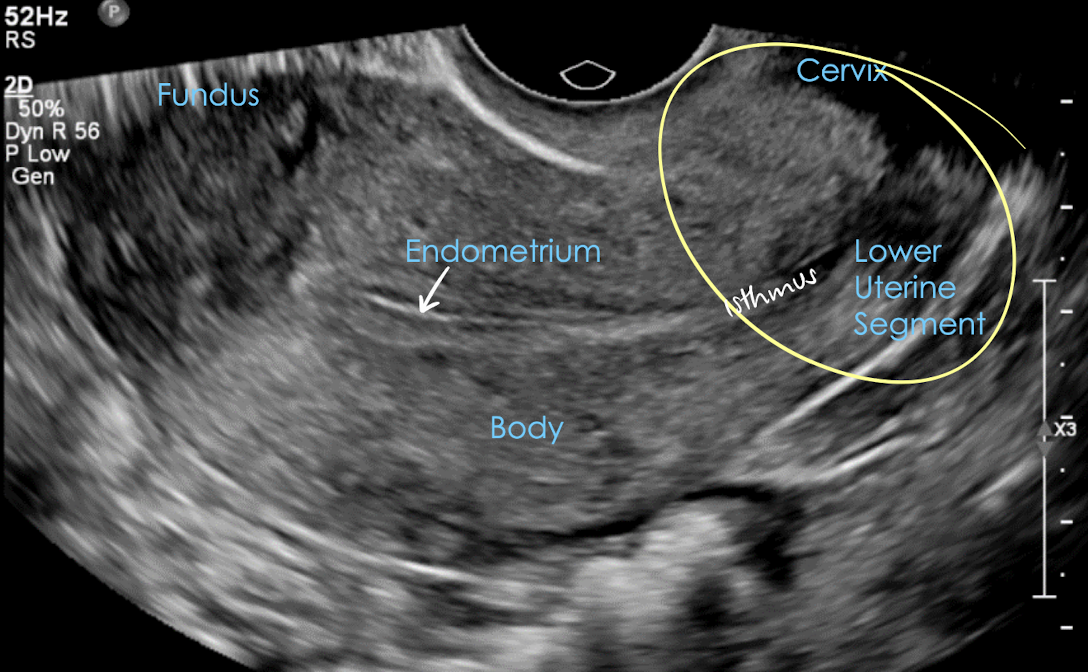

isthmus

narrow portion between uterine body and cervix

point where uterus bends anteriorly or posteriorly with an empty bladder

isthmus is the narrow region connecting the main uterine body to the cervix

LUS

lower uterine segment (LUS)

lower portion of uterus

includes: internal os, cervical canal, and external os

A?

transvaginal pelvic anatomy in LONG

** patient must empty bladder